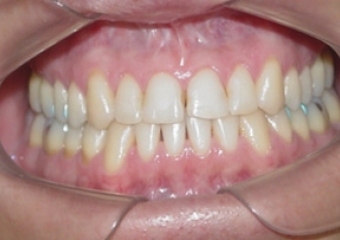

Mordida inicial

Mordida após a cirurgia

Mordida final após a remoção do aparelho